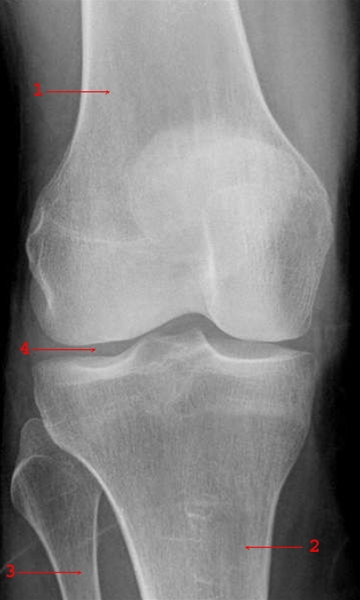

Knæet forbinder lårbenet med de 2 underbensknogler (se figuren nedenfor - skinnebensknoglen (2) og lægbenet (3)). Mellem lårbenet (1) og skinnebenet ligger de 2 menisker (4) som beskyttende bruskskiver, der tager af for stød (se tegning).

Røntgenbillede af knæ, front

Leddet stabiliseres af de 2 kraftige korsbånd og sideledbånd på ydersiden og indersiden af knæet.